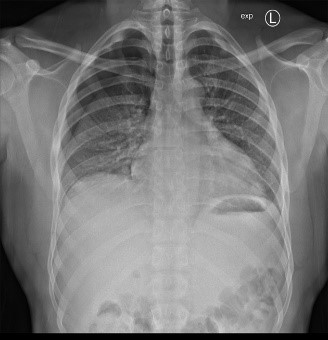

Inteventionelle Radiologie-Teil der Diagnostischen Radiologie oder ein eigenständiges Fachgebiet?

Die Entwicklung und Integration der interventionellen Radiologie im klinischen Alltag wird weltweit unterschiedlich gehandhabt. Während sie in den USA bereits als eigenständiges Fachgebiet anerkannt ist, gilt sie in Deutschland nach wie vor als fakultatives Teilgebiet innerhalb der Radiologie.

In der interventionellen Radiologie beschränkt sich die Tätigkeit des Radiologen nicht allein auf die bildgebende Diagnostik. Vielmehr übernimmt er eigenständig minimalinvasive Eingriffe und trägt dabei die Verantwortung für die prä-, peri- und postoperative Versorgung der Patient: innen.

Mit diesem Wahlfach möchten wir Ihnen praxisnahe Einblicke in das vielseitige und verantwortungsvolle ärztliche Arbeiten in der interventionellen Radiologie ermöglichen.